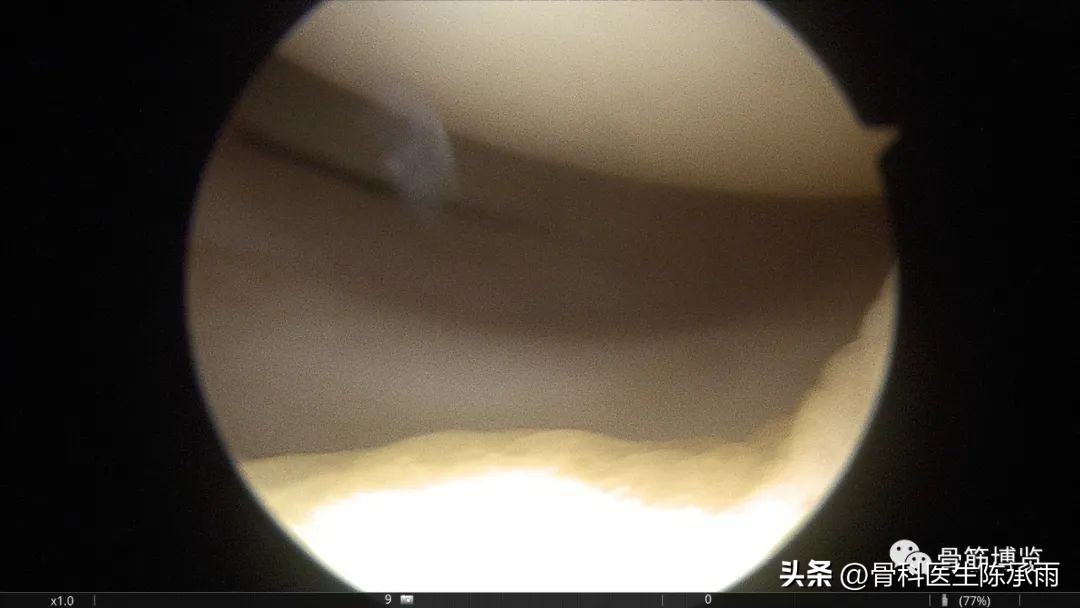

术中情况

探查前后交叉良好

股骨外侧髁关节面小块脱落

髌骨内侧间隙增大,髌骨外脱位,麻醉后检查膝关节伸屈时明显有脱位复位征,对侧膝关节良好

外侧半月板前角撕裂,从外向内缝合合1针固定